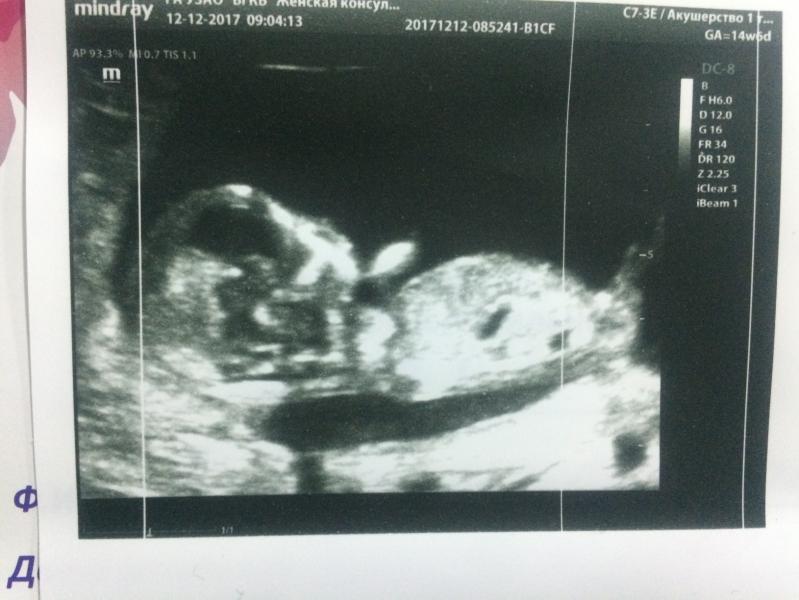

На первом скрининге увидела своего малыша 👼🏻 пол пока не известен, хочу подождать до второго скрининга) хорион прикреплён по задней стенке, поэтому животика у меня почти не заметно)